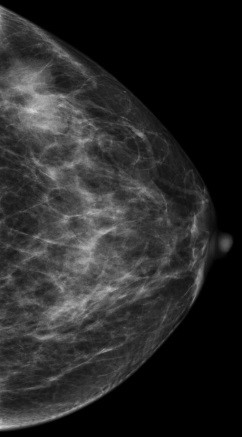

V-preview图像: